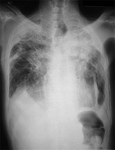

RT de asbestosis

De la colección personal de Kenneth D. Rosenman, Michigan State University